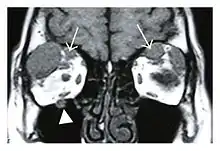

Swelling of the left superior and lateral rectus muscles, a mass lesion around the left optic disc (arrow), and enlargements of the left supraorbital nerve and the right infraorbital nerve (arrow heads) in a 60-year-old man with a serum IgG4 of 463 mg/dL.[1] (T1-weighted MRI)

Bilateral supraorbital nerve enlargements (arrows) and right infraorbital nerve (arrow head) enlargement in a 47-year-old woman with a serum IgG4 of 1000 mg/dL.[1] (T1-weighted MRI)